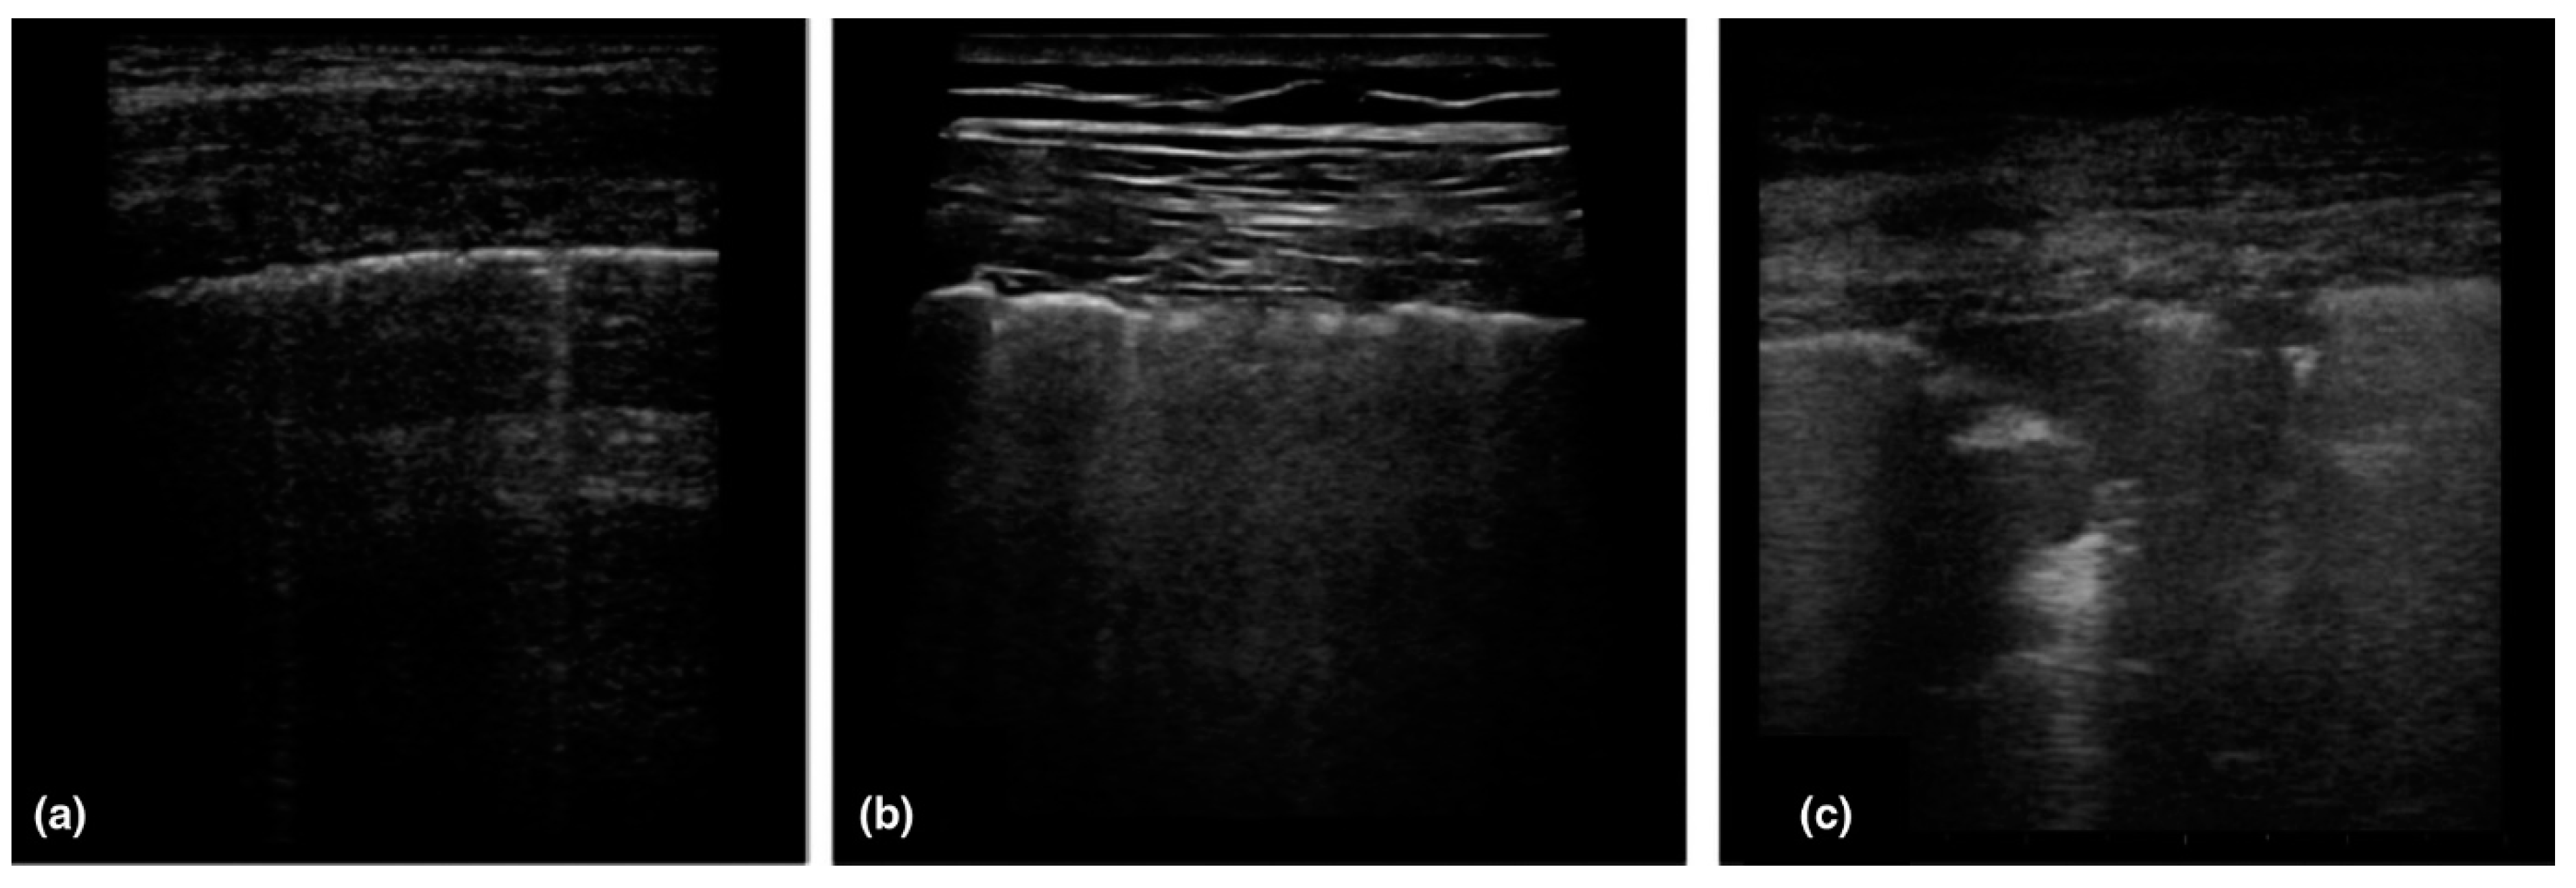

- Huanh, Y.; Wang, S.; Liu, Y.; Zhang, Y.; Zheng, C.Z.Y. A preliminary study on the ultrasonic manifestations of peripulmonary lesions of non-critical novel coronavirus pneumonia (COVID-19). BMC Med. 2020, 10, 1–14. [Google Scholar]